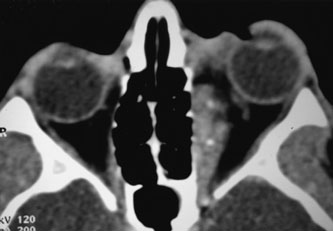

Most capillary hemangiomas can be diagnosed readily by clinical inspection. However, if delineation of the extent of deep orbital involvement is required, or the diagnosis is unclear, magnetic resonance imaging (MRI) with surface coils, gadolinium–pentetic acid enhancement, and fat suppression (to detect enhancement against the orbital fat) is indicated. The tumor is isointense to muscle and gray matter on T1- and hyperintense on T2-weighted images.22 The enhancement seen with intravenous contrast varies from moderate to intense and may be homogeneous or inhomogeneous.10 Lesions undergoing involution are less intense and more inhomogeneous. Major feeding vessels appear as black, serpiginous structures because of the “flow void” phenomenon.22 B-scan ultrasonography shows a smooth, lobular, or irregular mass with variable internal reflectivity that blends into surrounding orbital structures.23 A-scan ultrasonography shows alternating high internal reflectivity (high echo spikes) and low internal reflectivity (low echo spikes) resulting from the variable architecture and acoustic interfaces of vascular spaces, cellular areas, and septa, and moderate sound attenuation.24 High vascular flow may be demonstrated on Doppler echography. On computed tomography (CT) scan, the margins of deep infantile hemangiomas vary from moderately well defined to irregular.25 They can occur anywhere within the orbit and may be both intraconal and extraconal. There are no calcifications within these lesions. Occasionally, they indent the globe and are associated with bony orbital enlargement without erosion.10 Very rarely, angiography may be needed in the unusual situation where hazardous superselective embolization is used for life-threatening hemangiomas unresponsive to other therapies.20 These lesions frequently have multiple feeding vessels from both the internal and external carotid arteries.